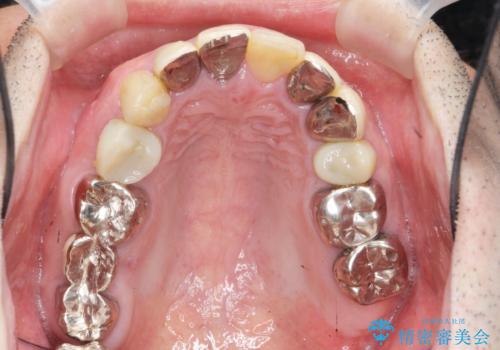

- 「少しずつ色々な箇所が悪くなり、歯医者に通い続けている。全ての歯を長持ちするような状態にできるような治療を受けたい。」、と全顎・総合的な治療を希望され来院されました。

根管治療・矯正治療・歯周外科・セラミック補綴を含む様々な治療オプションを駆使し、長期間良好な状態に保てるような治療計画を立案します。

矯正治療を絡めた総合的な治療をお行なったことで、理想的な咬合関係を確立し安定した噛み合わせで仕上げることができました。

また歯周外科を行うことで歯ぐきの腫れを改善し、清掃性を高めています。